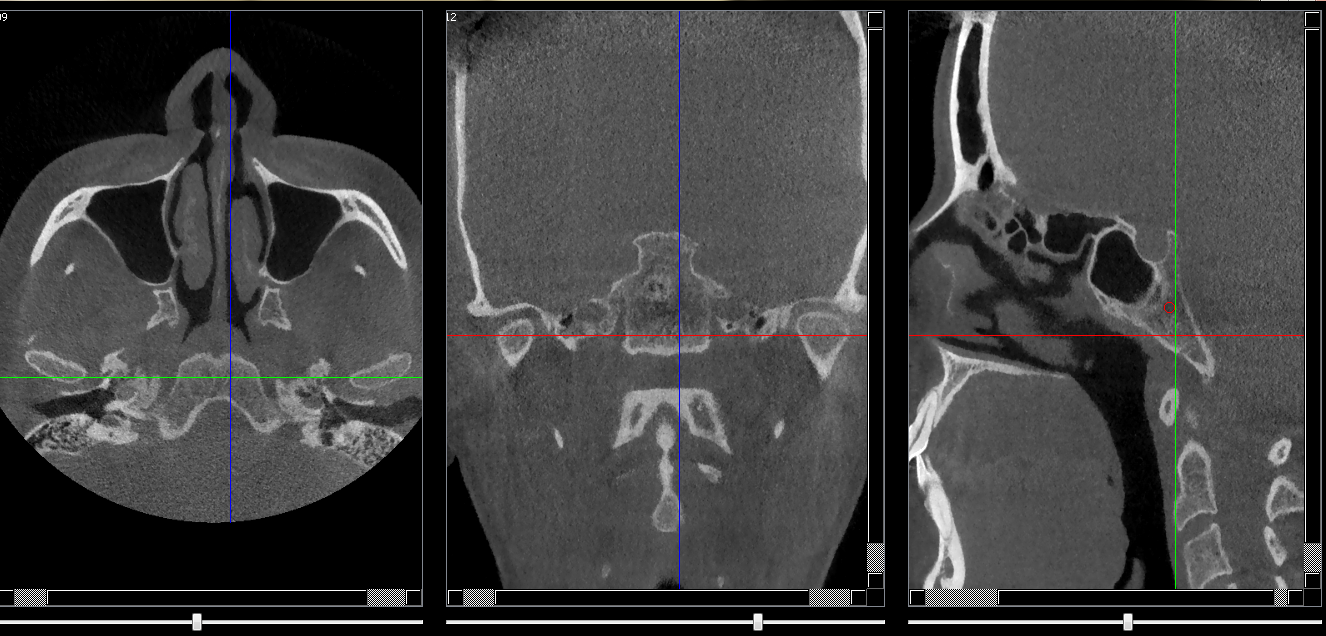

Condyles

Coupe de 0.15 mm passant par le centre des fosses mandibulaires montrant les condyles